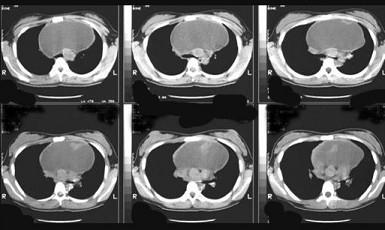

问题 18岁,男,咳嗽头晕一个月,请结合胸片和CT检查,选出最可能的诊断 ( )

选项 A、胸内甲状腺瘤 B、神经源性肿瘤 C、淋巴瘤 D、畸胎瘤 E、胸腺瘤

答案 D